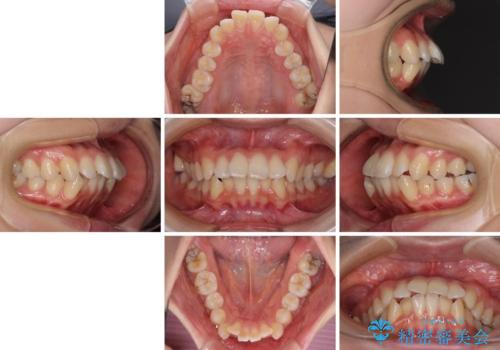

- 前歯のデコボコや口元の突出感、口の閉じにくさを気にして来院された患者様です。

上下左右第一小臼歯4本を抜歯し、ワイヤー装置にてデコボコを解消しながら口元を引っ込めるよう矯正治療を行うこととしました。

抜歯スペースを閉じている過程で、左側の上下犬歯が引っかかってしまい、進捗が停滞しましたが、当初予定の2年~2年半の間で無事に治療を終えることができました。